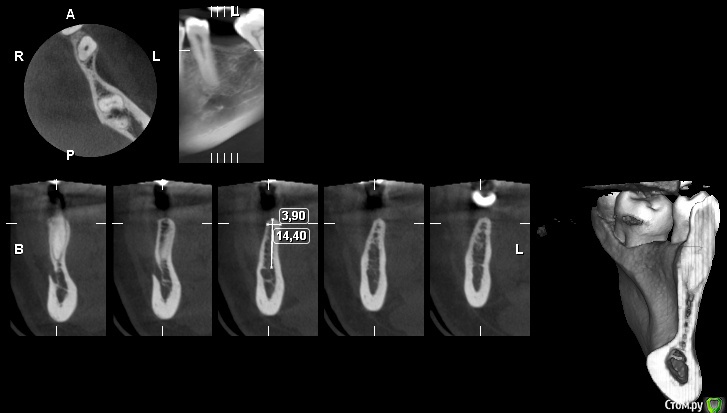

gum Опубликовано 16 октября, 2015 Поделиться Опубликовано 16 октября, 2015 Есть КТ нужен совет возможно ли расщепление или просто НКР. Блоками пока не приходилось работать(( Ссылка на комментарий

Михалыч007 Опубликовано 16 октября, 2015 Поделиться Опубликовано 16 октября, 2015 Немного смущает медиальный наклон коронки 6 .Я бы вообще по Кури сделал . Скорее всего кусок отлетит, как только начнете расщепляться, а если и повезет и установите имплант,то он даст резорбцию в апикальной части(кости недостаточно).Как вариант-попробывать по-Пономарёвски. Сходите к нему на курс-оч.душевный чел. На все вопросу отвечает,даже не по теме.Хотя и сосиска,если она размером с ливерную колбасу должна вполне сработать. Ссылка на комментарий

St_Klaus Опубликовано 18 октября, 2015 Поделиться Опубликовано 18 октября, 2015 Скорее всего кусок отлетит, как только начнете расщепляться, а если и повезет и установите имплант,то он даст резорбцию в апикальной части(кости недостаточно).. Именно так у меня и получилось как-то раз в очень похожих условиях. И кусок отлетел, и резорбцию получил. Топикстартеру: если хорошо владеете навыком расщепления, то делайте; если нет, то лучше НКР. Ссылка на комментарий